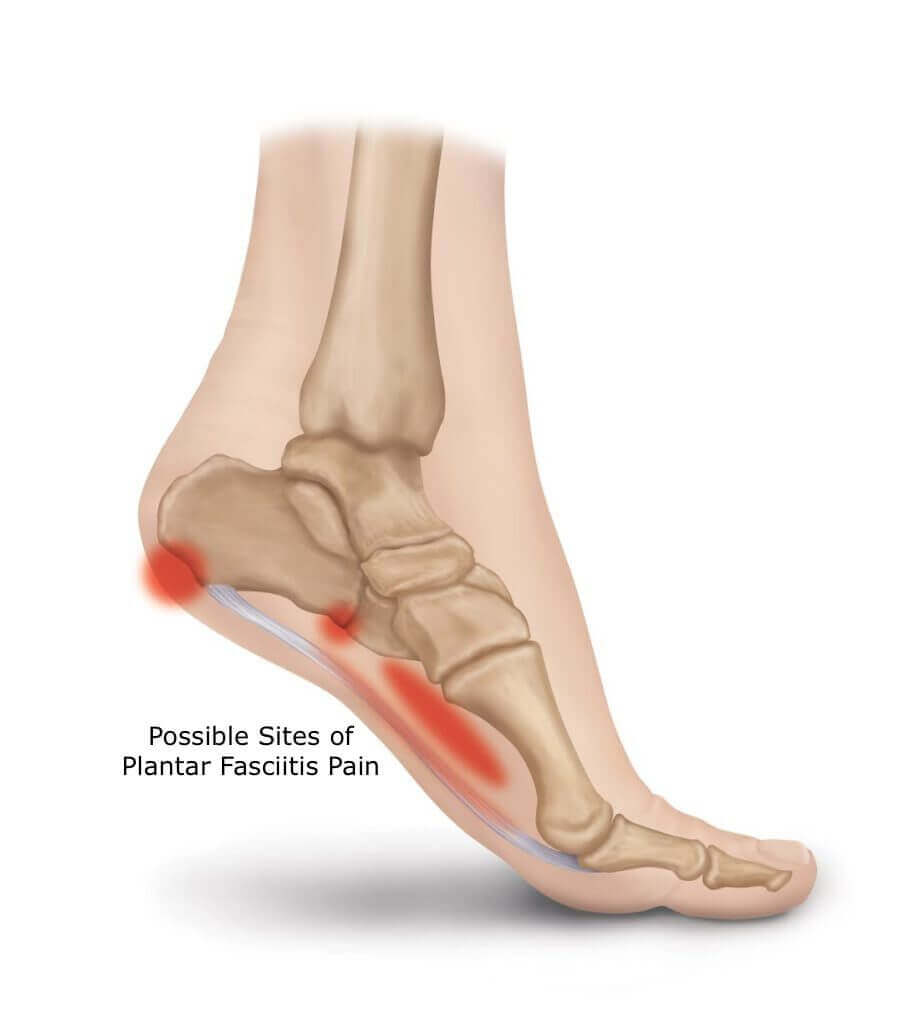

족부 통증은 다음과 같은 부위에서 발생할 수 있는데, 대게는 뒷꿈치쪽 근위부의 통증을 호소하게 됩니다.

통증은 주로 극한된 부위에서 느껴지고, 아침에 첫 걸음에서 심하게 느낍니다. 생활을 하면 증상은 일시적으로 약간 좋아지나, 장기적으로 계속 아픈부위를 자극주고 사용하게 되면 점차 악화됩니다.

근위부의 경우 족저근막 이라는 인대가 붙어 있는 부위 위기 때문에 날카롭게 뼈모양이 변하는 골극이 발견되는 경우 족저근막염이 쉽게 발견될 수 있습니다.